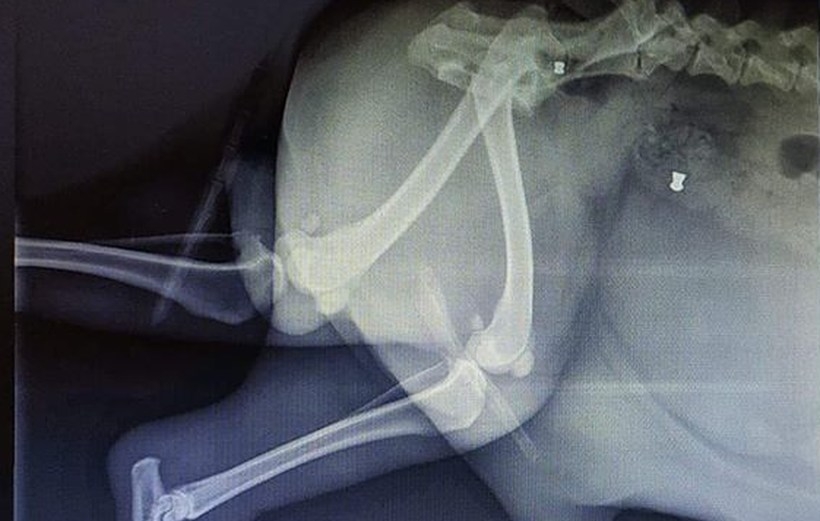

Nasz pies ma wbite 2 śruty. Pies nie kwalifikuje się do operacji. Bardzo cierpi. Ma założony cewnik, jest napuchnięty w tylnej części ciała ma uszkodzone nerwy z tego względu nie może chodzić. Prawdopodobnie zostanie uśpiony. Dwóch lekarzy powiedziało, że nie podejmie się operacji – opisuje zdarzenie pan Paweł i prosi o informację, czy już ktoś w regionie był w podobnej sytuacji.

Jak mówi nam Czytelnik, który przesłał fotografie prześwietlenia swojego psa, na zdjęciu widać dwa rodzaje śrutu.

Nie trzeba być balistykiem żeby dopatrzyć się, że pies został postrzelony od góry. Wydaje mi się, że z dwóch wiatrówek – mówi nam właściciel psa.